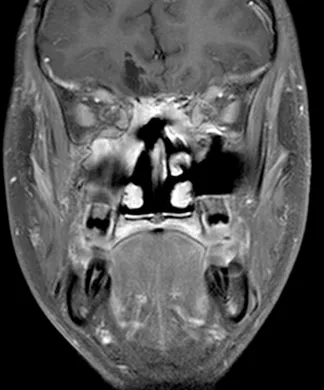

脑部和鼻旁窦计算机断层扫描(CT)和磁共振成像(MRI)扫描显示右侧存在5.5×4.4×5.6厘米肿块,起源于鼻腔、筛窦和蝶窦区域。肿块已侵蚀筛板进入前颅窝。该肿块在CT扫描上未出现钙化(图1),与脑组织等密度,伴有不均匀对比增强。肿块在T1和T2加权MR图像上(图2、3、4)与脑组织等信号,钆增强后显示不均匀强化。注意到周围存在血管源性脑水肿和占位效应。脊柱MRI未见转移证据。

图2:冠状位T1加权钆增强MRI扫描,证实起源于鼻腔并延伸至前颅窝的大肿瘤团块。对额叶下部的占位效应和轻微中线移位明显可见。

图4:冠状位T2加权MRI扫描,证实颅内肿瘤成分的不均匀实性和囊性性质。病灶周围水肿以及肿瘤相关的中线移位清晰可见。